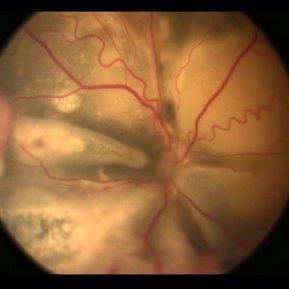

Stage 3 Coats' Disease

Fundus photography of a 6 months old baby boy who presented with unilateral leucoria. There was right exudate retinal detachment with extensive hard exudates and tortuous retinal vessels. Diagnosis of Coats' disease was made that was externally drained and intravitreal rhanibizumab was given.

Condition/keywords: Coats' disease, exudative retinal detachment, exudative retinopathy, unilateral exudative retinal detachment